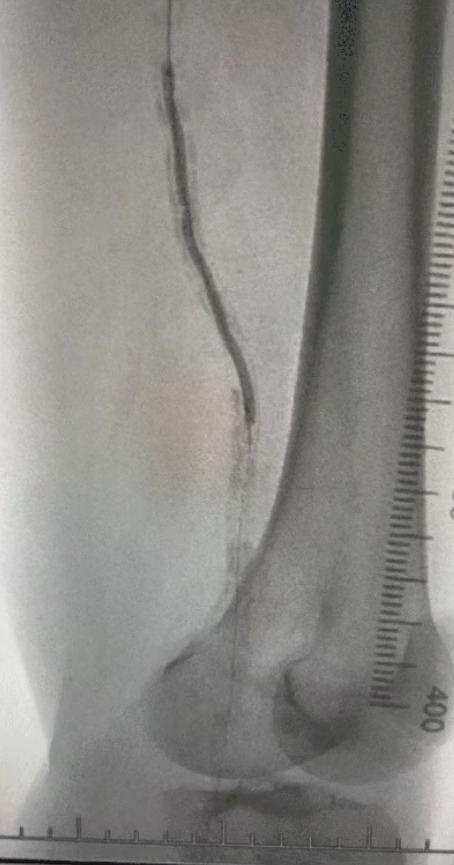

Given the complex vascular condition, we selected the ThorCrack Peripheral IVL Balloon Dilatation Catheter System. Due to the patient’s limited tolerance, staged interventional procedures on both lower limbs were performed.

Post-procedure, arterial stenosis improved significantly, blood flow increased, and skin temperature rose. No postoperative complications occurred. Both the patient and surgical team were highly satisfied with the results.